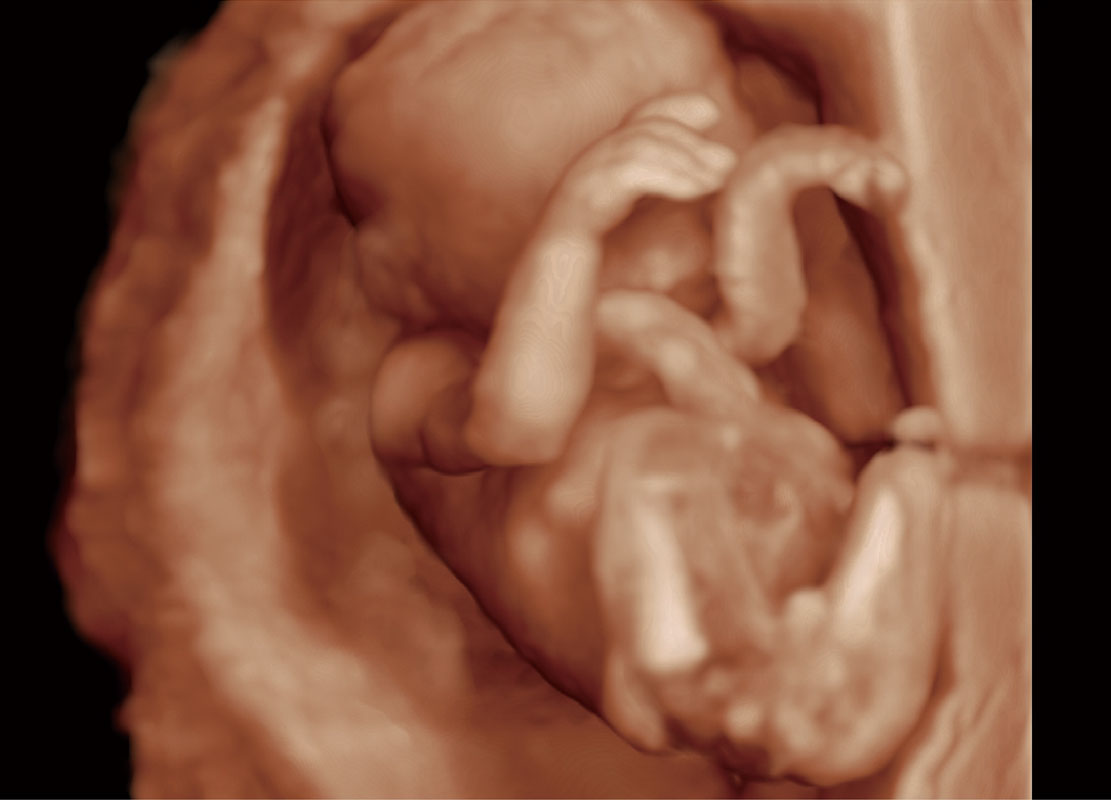

胎心筛查

P60搭载一系列胎儿心脏成像技术,实现精细的胎儿心脏评估。

• 胎心容积成像

中晚孕筛查

P60提供简单易学易用的高端诊断工具,为您中晚孕筛查提供快速清晰的解剖信息。